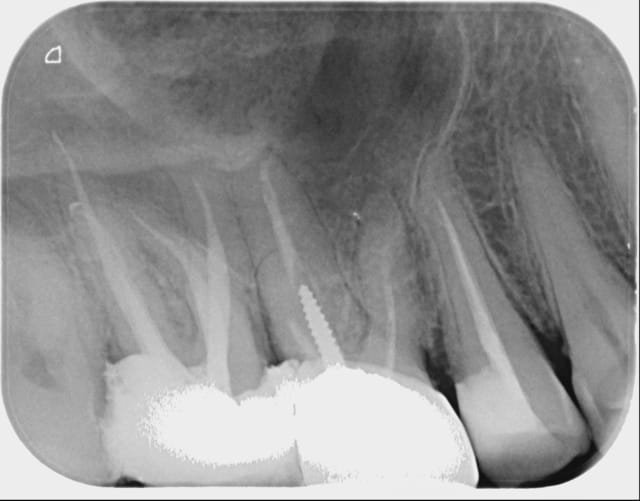

une 17 avec 2 racines palatines!

Franchement j'en avais jamais vu! acte rémunéré 80 euros et des bananes... vu le temps passé. Faut la foi... j'ai fait ma bonne action...

Ben c'est la période j'en ai vu une la semaine dernière! Sympathique les 5 canaux ^^